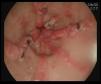

He was admitted to the hospital with an episode of blood in stool and evidence of anemia. Endoscopic study revealed vascular-like lesions in antrum converging as they neared the pylorus, compatible with watermelon stomach1,2 (Fig. 1). In the presence of active bleeding, he was treated with argon plasma coagulation3 (Fig. 2).

Gastric antral vascular ectasia (GAVE) is a rare, but serious, cause of upper gastrointestinal bleeding (4% of all gastric hemorrhages). The endoscopic findings are characteristic: linear images, oriented radially and converging on the pylorus (watermelon stomach1,4).